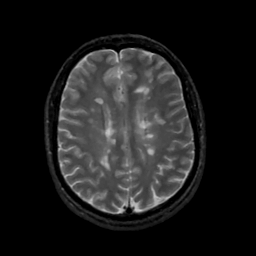

MR Study #12, May 12, 1991 -- Slice #33

[Home][Help][Clinical][Tour 1][Tour 2] Slice 33